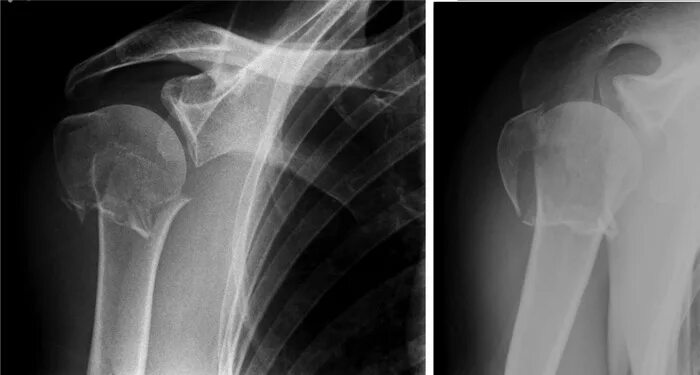

Оскольчатый перелом плеча со смещением